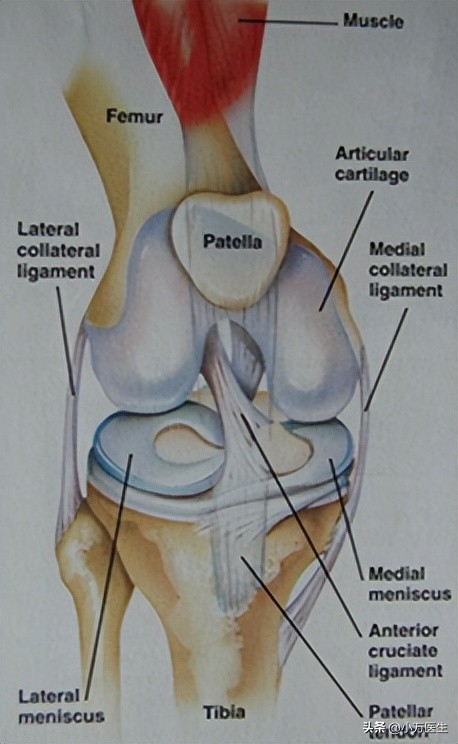

解剖

半月板位于胫骨平台表面,为软骨组织,分为内侧半月板和外侧半月板。半月板周边厚,中央薄,截面呈三角形,周边附着于关节囊,中部游离,上表面凹陷,与股骨髁形成相对面,下表面平,位于胫骨表面。

内侧半月板呈“C”形,分为前、后角和体部,前角附着于前交叉韧带前方,后角附着于后交叉韧带前方,前角发出半月板横韧带与外侧半月板前角连续,后角比前角宽大。内侧半月板前角与关节囊和脂肪垫之间不连接,体部与后角与关节囊紧密相连,内侧半月板与内侧副韧带深层(关节囊韧带)和半膜肌相连,又借半月板髌骨韧带与髌骨相连,因而活动度小,易于损伤。外侧半月板呈“O”形,也分为前角、体部和后角。前后角止点很接近,前角止于前交叉韧带后方,并与其相延续;后角止于内侧半月板后角止点的前方。外侧半月板与胫骨平台结合并不紧密,体部与后角交界处又有腘肌腱裂孔,因而外侧半月板活动度相对较大,较内侧半月板不易损伤。

(1、外侧半月板;2、内侧半月板)